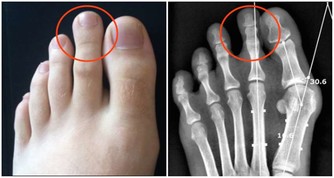

4.膝關節炎

膝關節炎是一種由膝關節軟骨退行性改變引起的疾病,引起疾病的原因包括年齡、性別、遺傳因素、重複性關節應激和代謝紊亂,病變影響軟骨、軟骨下骨和關節組織,主要特徵為關節軟骨的漸進性破壞與軟骨下骨的硬化,骨贅形成,與滑膜炎有關,臨床症狀表現為劇烈疼痛、關節僵硬、關節活動度顯著降低,有甚者可能進一步導致殘疾發生,嚴重影響患者的生活質量。

除此之外,常見的還有痛風、肥胖、風濕性關節炎以及類風濕性關節炎等都會引起“膝蓋”疼,由此可見,我們需要對此引起高度的重視,做到“早發現,早治療”,防止由於個人忽視導致疾病逐漸加重、惡化,進而對家庭和日常生活產生不良影響。